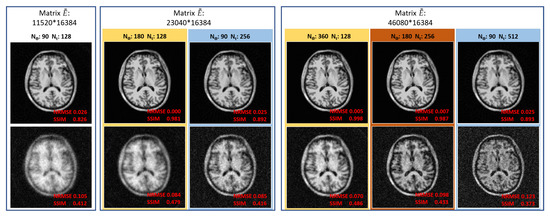

| = 90, = 128 | 4096 MB | 2880 MB | 0.1758 MB | 6976 MB |

| = 180, = 128 | 4096 MB | 5760 MB | 0.3515 MB | 9856 MB |

| = 90, = 256 | 4096 MB | 5760 MB | 0.3515 MB | 9856 MB |

| = 360, = 128 | 4096 MB | 11,520 MB | 0.7031 MB | 15,617 MB |

| = 180, = 256 | 4096 MB | 11,520 MB | 0.7031 MB | 15,617 MB |

| = 90, = 512 | 4096 MB | 11,520 MB | 0.7031 MB | 15,617 MB |